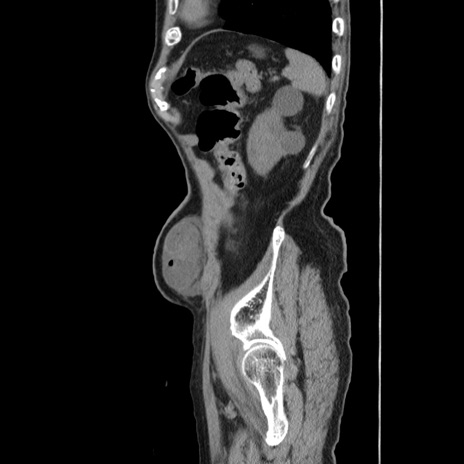

症例24(矢状断像)

【症例】80歳代男性

【主訴】左側腹部痛、嘔吐

【現病歴】本日早朝より左腹部に痛みあり。昼頃嘔吐認めたため、救急要請。

【既往歴】直腸癌(Mile手術)、胆摘

【身体所見】意識清明、BT 35.9℃、BP 221/93mmHg、SpO2 97%(RA) 、腹部:左ストーマ周囲に限局性の腹部膨隆あり。 膨隆部自発痛・圧痛あり・軟。